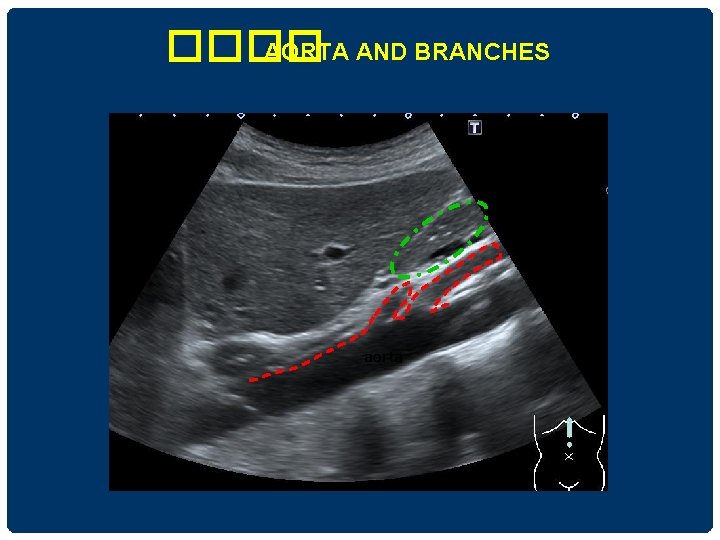

���� AORTA AND BRANCHES aorta